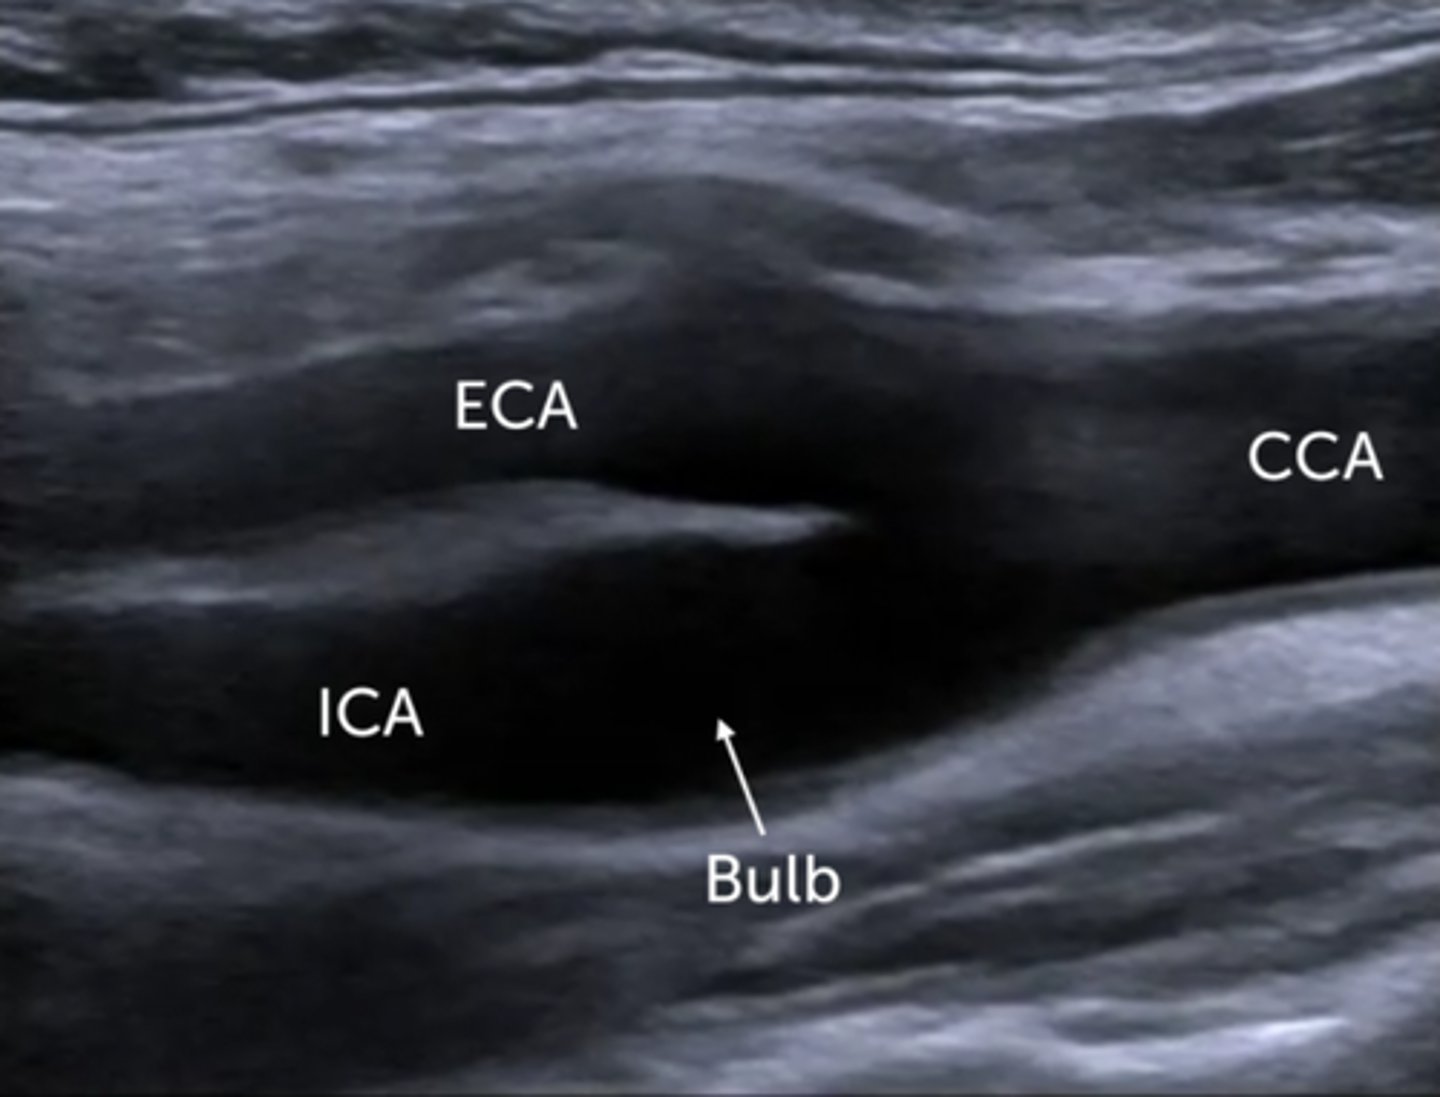

Common carotid arteries:

-Left originates from the _____

-Right arises from the _____

-Ascend the _____ aspect of the neck

-Lie _____ to the internal jugular vein and _____ to the thyroid lobe

-Course deep to the _____ muscles

-Typically, no _____

-Bifurcate into the _____ and _____ carotid arteries

-Left originates from the aortic arch

-Right arises from the innominate (brachiocephalic) artery

-Ascend the anterolateral aspect of the neck

-Lie medial to the internal jugular vein and lateral to the thyroid lobe

-Course deep to the sternocleidomastoid muscles

-Typically, no branches

-Bifurcate into the external and internal carotid arteries

External carotid arteries:

-Supplies the ____, ____, and ____ with blood

-Lies _____ and _____ to the ICA

-Multiple extracranial _____

-_____ is the first branch of the ECA

-Supplies the neck, scalp, and face with blood

-Lies anterior and medial to the ICA

-Multiple extracranial branches

-Superior thyroid artery is the first branch of the ECA

Internal carotid arteries:

-Main blood supply to the _____ and _____

-Lie _____ and _____ to the ECA

-Terminate at the _____

-No _____ branches

-_____ is the first branch of the ICA

-Main blood supply to the eyes and brain

-Lie posterior and lateral to the ECA

-Terminate at the circle of Willis

-No extracranial branches

-Ophthalmic artery is the first branch of the ICA

Sonographic Appearance:

-Parathyroid glands are flat, bean-shaped _____echoic structures located _____ and _____ to the thyroid lobes

-Salivary glands - ____geneous and ____echoic compared with the normal surrounding muscle. Degree of echogenicity depends on the amount of intraglandular _____ tissue

-Carotid arteries and jugular veins appear as ____echoic tubular structures demonstrating internal _____

-Parathyroid glands are flat, bean-shaped hypoechoic structures located posterior and medial to the thyroid lobes

-Salivary glands - homogeneous and hyperechoic compared with the normal surrounding muscle. Degree of echogenicity depends on the amount of intraglandular fatty tissue

-Carotid arteries and jugular veins appear as anechoic tubular structures demonstrating internal vascular flow